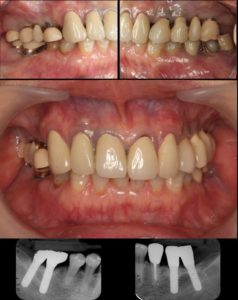

2003.2 治療終了時 61歳

以前下に入れ歯を作りましたが違和感のため使用できなかった為、インプラント治療で義歯を回避することにしました。